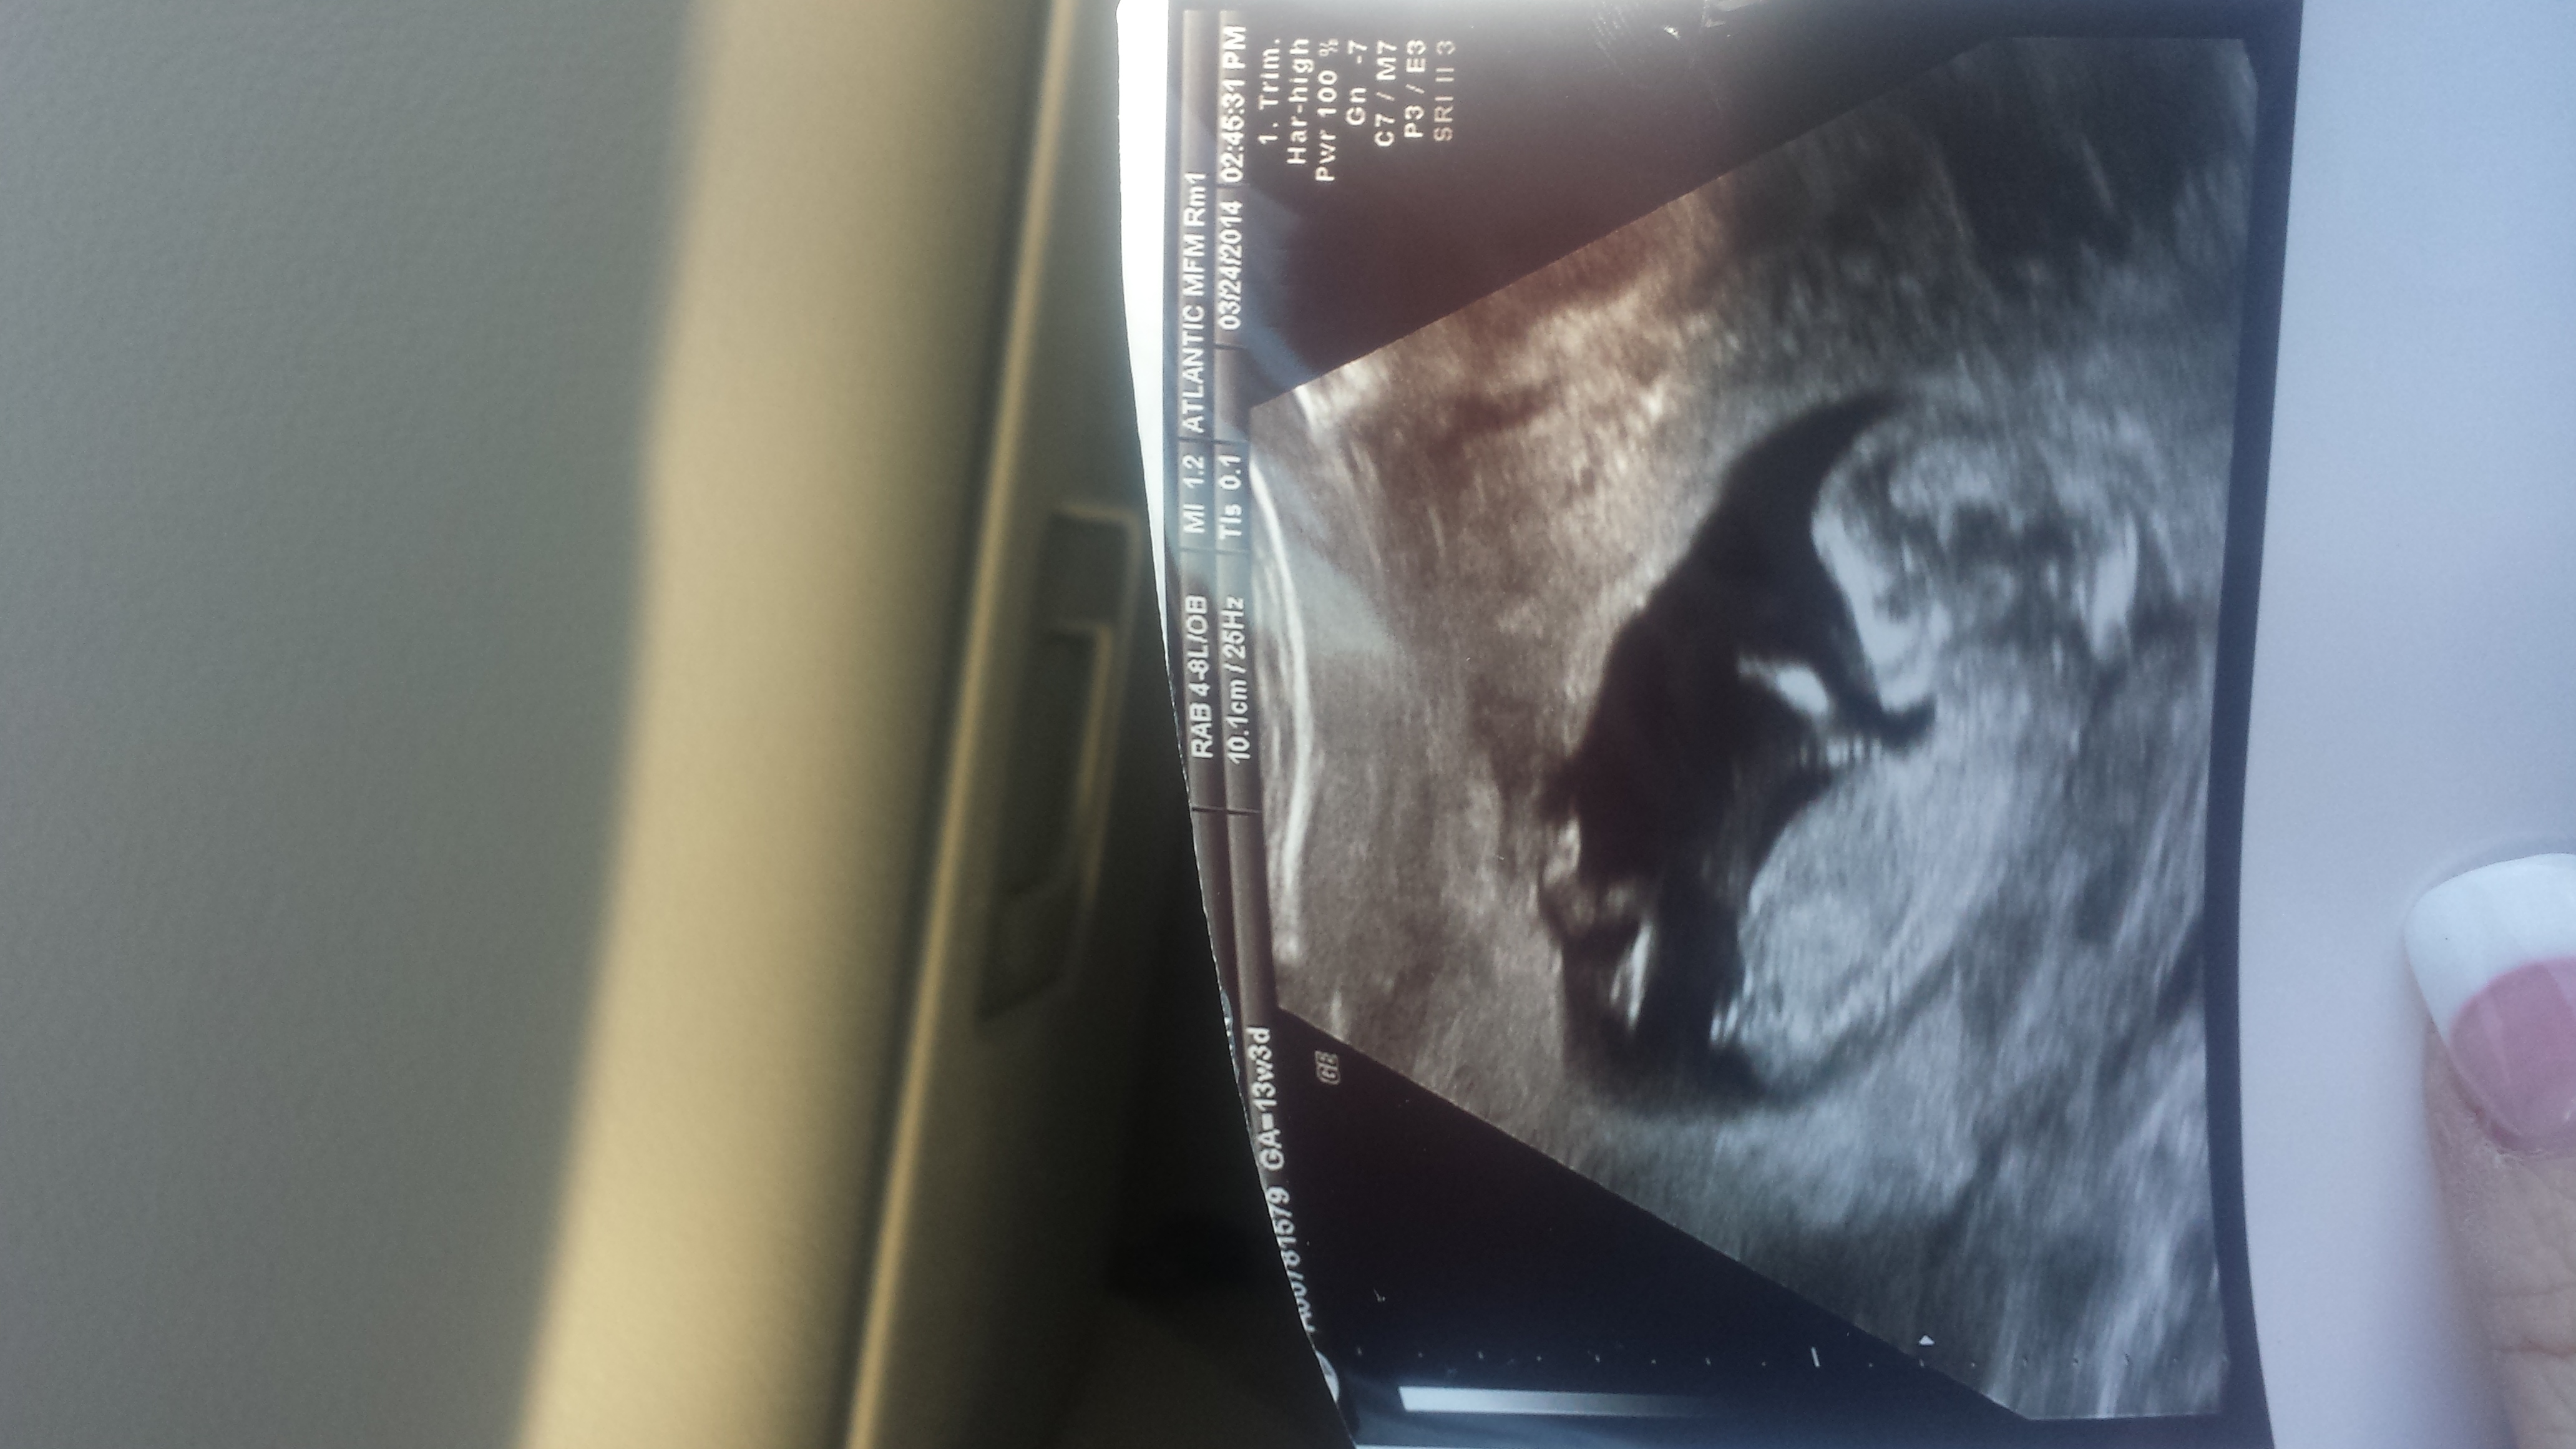

By LMP I should be 13 weeks 2 days but baby is measuring 12 + 4....any nub guesses very appreciated! Attachment 17800Attachment 17801

Thank you all! This is a zoomed rotated pic if its better for guesses....I was kind of hoping girl but having my son have a brother wouldn't be bad either as I see the nub looking boyish too!

It looks very much like a boy nub. Congratulations!